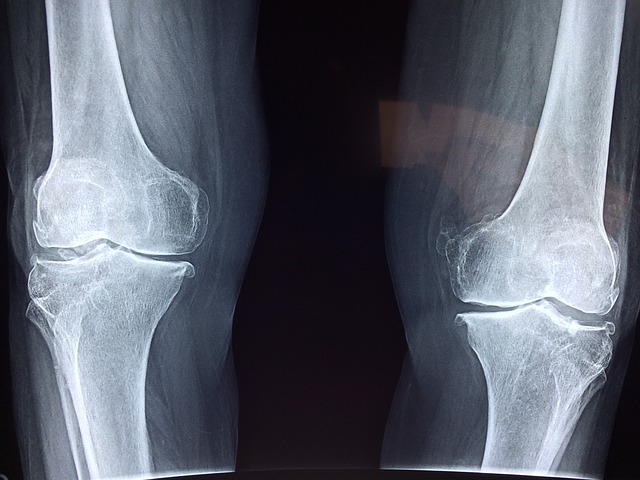

2.1 퇴행성 관절염(골관절염) 초기 증상

퇴행성 관절염은 노화나 반복적인 관절 사용으로 인해 연골이 닳아 발생합니다. 주로 무릎, 엉덩이, 손가락 관절에서 자주 나타납니다.

A4. 아침에 경직이 1시간 이상 지속되거나, 양손과 양발에 대칭적인 통증과 붓기가 나타나면 류마티스 관절염을 의심해보아야 합니다. 조기에 병원을 방문해 혈액 검사와 영상 검사를 받는 것이 좋습니다.